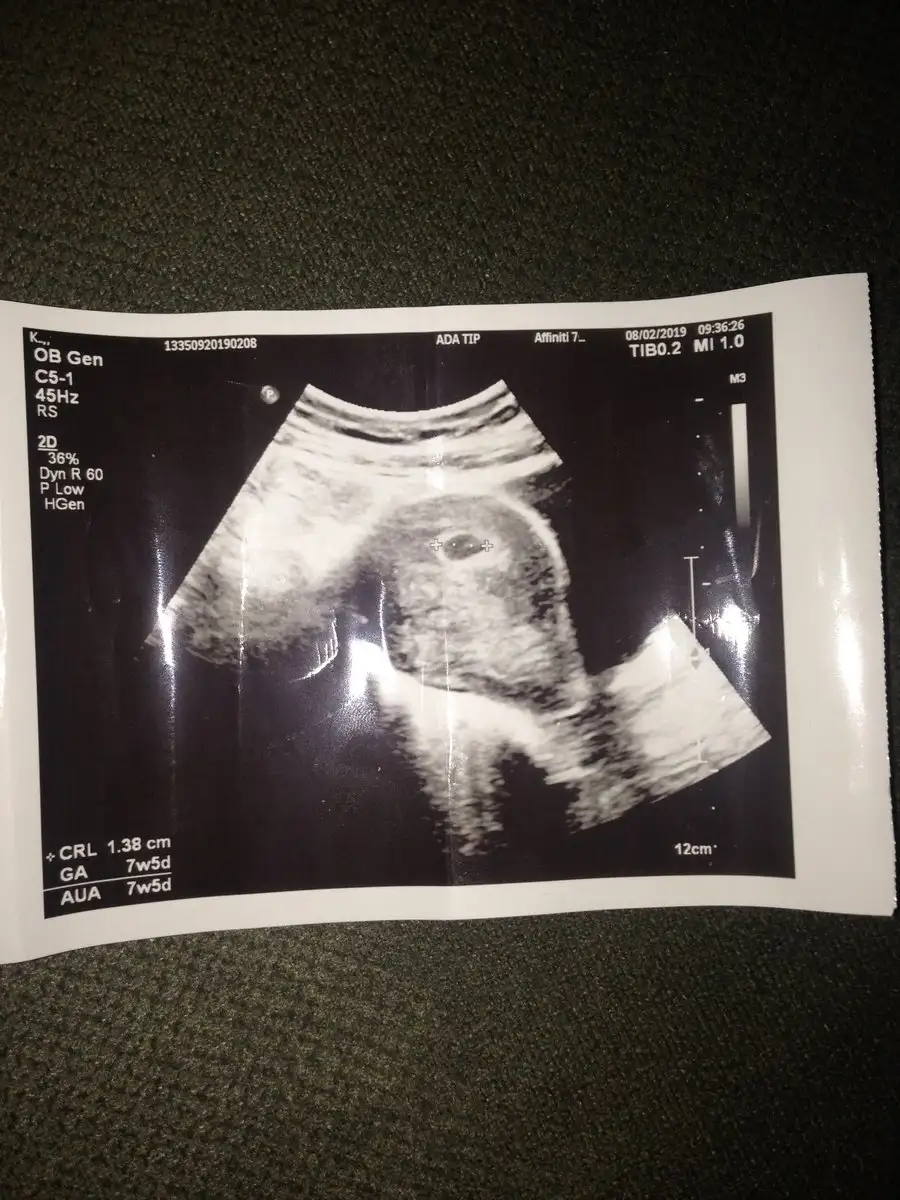

Aynı şeyler diye geçiyor zaten şu an bebeği ölçmek imkansız tabi ki,ölçümde kullanılıyor,ya benim ultrson kağıdımda 7+5 yazıyo haftamı çok tuhaf,çok donanımlı güvendiğim bi hastane ve kendi doktorum olmasa çoktsn başka yer araştırırdım